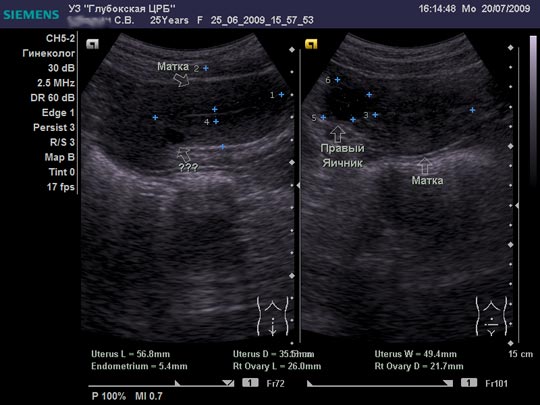

Женщина 25 лет предъявляет жалобы на периодически возникающую болезненность в нижних отделах живота, боли появились около 6-8 мес. Менструальная функция не нарушена. В анамнезе кесарево сечение, ребёнку 2,5 года.

Doc, на взгляд неспециалиста в гинекологическом УЗИ - Nabothian cyst

Я тоже думал про наботовы желёзки, но меня смутил тот момент, что не явилось ли это образование следствием оперированной матки, лигатуры... ну чего-то там с ними... или что-то в этом духе????

Согласен, Наботова или эндо-цервикальная киста шейки. Ничего специфического.

Naboti пишем, эндометриоз в уме

запросто. об эндометриозе надо думать, когда ov.nabotae несколько. и к тому же присутствуют гиперэхогенные линейные включенияDoc писал(а):Спасибо.